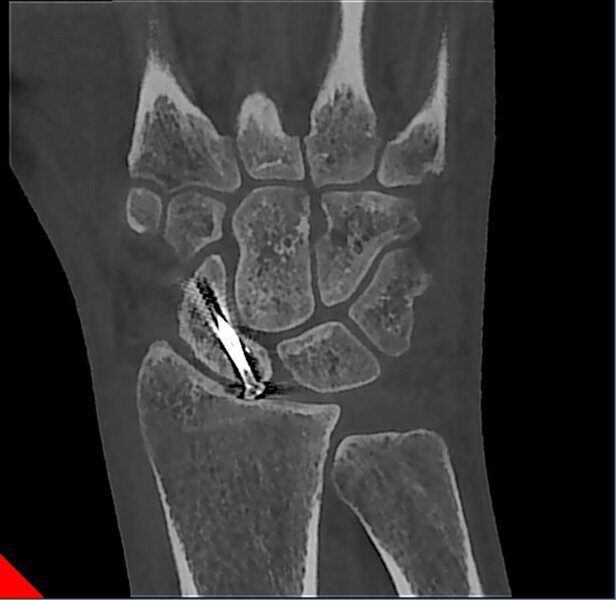

Fractura de escafoides con material de osteosíntesis.